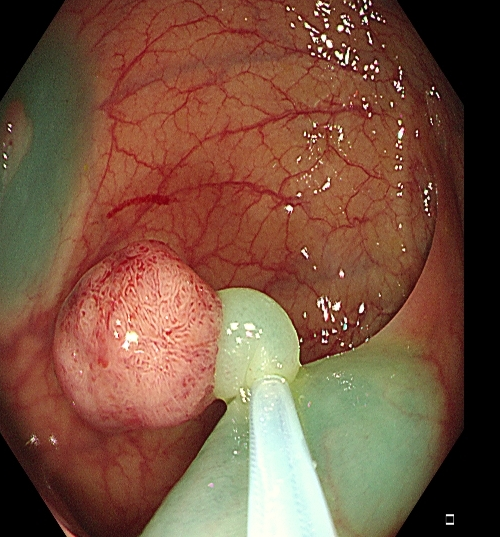

操作过程中应夹住息肉头端,适当上提(可避免损伤肌层),与肠壁保持适当距离,当息肉蒂部出现发白时,停止电凝,钳除病变。应注意是,切除息肉不易过大,否则会造成通电时间延长,增加全层损伤的风险(图1)。

图1 热活检钳除术示意图,A 钳除前,B 钳除后创面。C-D:热活检钳除术注意事项,息肉体积过大,增加电凝时间,造成透壁性损伤。